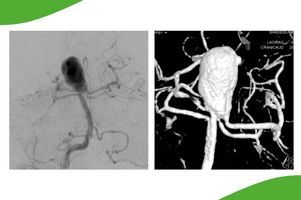

Großes Hirnaneurysma im Bereich der Arteria basilaris (sogenanntes Basilariskopf-Aneurysma), welches durch die raumfordernde Wirkung symptomatisch geworden ist.